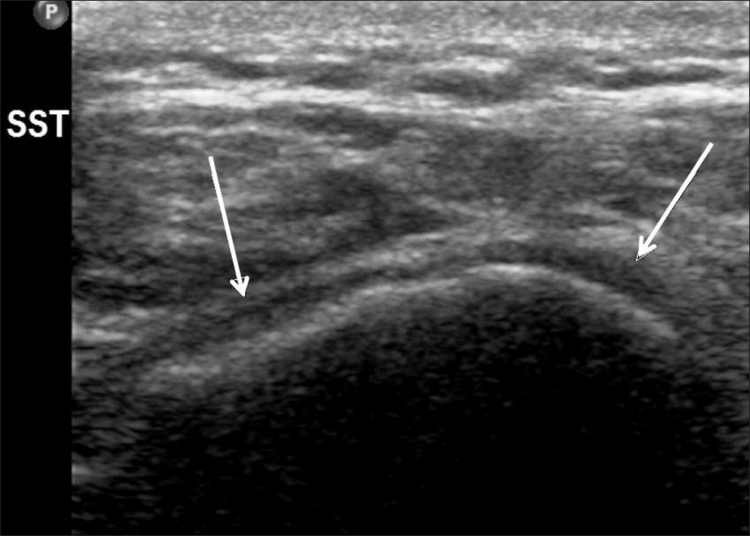

Los desgarros del manguito de los rotadores son la patología más común que se encuentra en los exámenes de ultrasonido del hombro.[7] La incidencia de lágrimas aumenta con la edad. Los desgarros de tendones se pueden clasificar de acuerdo con el grado de falla de la fibra, que van desde desgarros completos [Figura 7], desgarros de espesor total [Figuras 8, 9], desgarros de espesor parcial [Figuras 10-12] y desgarros intrasustancia [Figura 13 ]. Un desgarro agudo suele ir acompañado de derrame articular o bursal [Figura 12]. [7-9] La ausencia de derrame generalmente se relaciona con desgarros crónicos.[9] En un metanálisis sobre la precisión de la resonancia magnética, la artrografía por resonancia magnética y la ecografía en el diagnóstico de desgarros del manguito de los rotadores, la ecografía ofreció una alta sensibilidad y especificidad para la evaluación de los desgarros del manguito de los rotadores de espesor total (92,3 y 94,4 %, respectivamente) con 85,1 % y 92 %, respectivamente para todas las lágrimas.[7] El desgarro de espesor parcial aparece como un defecto o hendidura hipoecogénica en el tendón, afectando solo una parte de su espesor, mientras que un desgarro de espesor total se extiende desde la bolsa hasta la superficie articular del tendón. Un desgarro completo es un desgarro de espesor completo que afecta todo el ancho del tendón. El tendón se retrae medialmente, y la cantidad de retracción depende de la edad del desgarro. En las roturas crónicas, el tendón desaparece por debajo del arco coracoacromial, dejando la cabeza humeral descubierta por el supraespinoso, el denominado signo de la "cabeza desnuda". Los hallazgos de la ecografía incluyen la falta de visualización del tendón y la hernia del músculo deltoides. Los desgarros intrasustancia permanecen localizados en el tendón sin afectar sus márgenes. Los desgarros intrasustancia y de espesor parcial pueden ser difíciles de diferenciar de la tendinopatía focal.

Las patologías no relacionadas con desgarros del manguito rotador que se encuentran con más frecuencia son la tendinosis del manguito rotador [Figura 14], la tendinitis calcificante del manguito rotador [Figura 15] y el pinzamiento del tendón subacromial [Figura 16]. Vale la pena señalar que, en tales casos, se pueden desarrollar desgarros debido a la debilidad del tendón [Tabla 2].[79] La tendinosis o tendinopatía del manguito de los rotadores se presenta como inflamación del tendón con una ecotextura hipoecoica heterogénea del tendón. Las calcificaciones del manguito de los rotadores aparecen como focos hiperecogénicos, ya sea con una sombra posterior bien definida (Tipo I) o con una sombra tenue (Tipo II) o ausente (Tipo III). El Tipo I corresponde a la fase formativa y los Tipos II y III a la fase de reabsorción, en la que cambian a depósitos de calcio semi o totalmente líquidos. En el pinzamiento subacromial, el tendón no se desliza en el espacio subacromial durante la abducción y la elevación anterior del brazo.